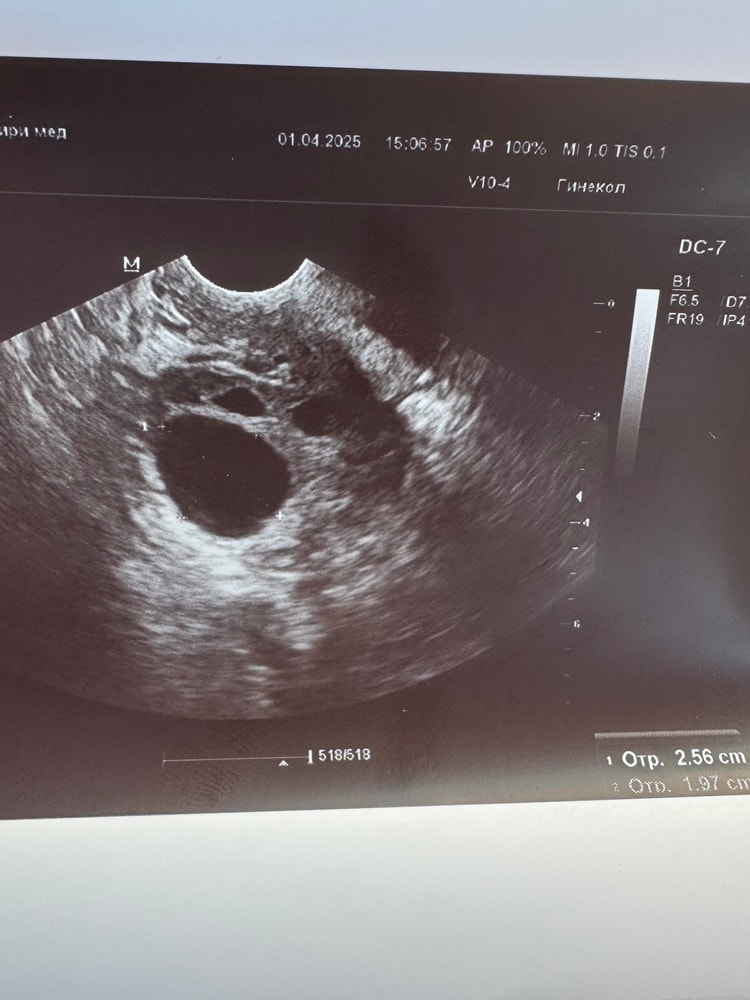

Лопнет ли фолликул размерами 25,6*19,7? Уколола овитрель, очень не хочу кисту. Или уже без вариантов? 😔 Читала блог, пишут 25 много, но когда два размера, вроде считают размер фолликула как (25,6+19,7)/2. Тогда он у меня 22,6. Капец какой-то, завтра на узи, а я что-то паникую.